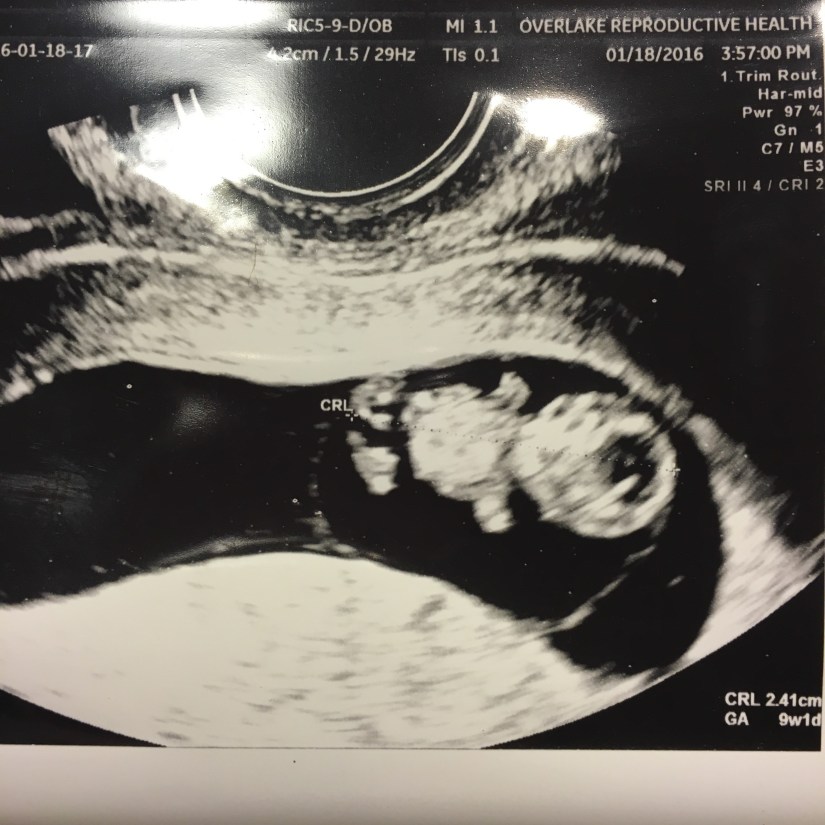

Here’s a progression of baby through the first trimester (we didn’t get a printout from our 13 week visit):

…And a bonus video from 12 weeks. We have another active baby! The jiggling at the end is because I laughed.